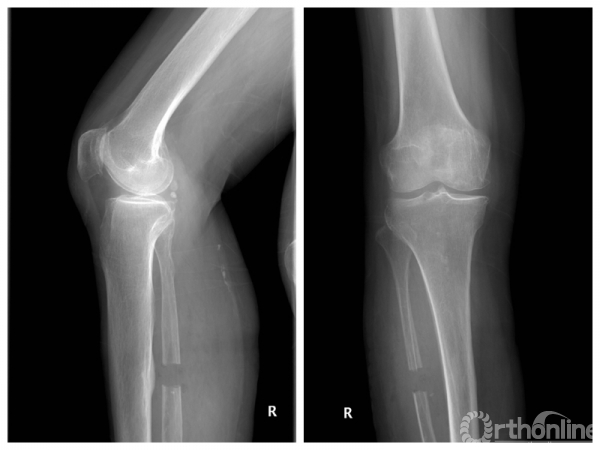

该手术经腓骨后外侧入路,自腓骨长短肌与比目鱼肌间隙钝性分离至腓骨,行骨膜下剥离后显露腓骨。于腓骨小头下方6 ~10 cm 处,截除约2cm长腓骨段,断端用骨蜡封堵,防止腓骨断端愈合,见图1~2。手术最主要的风险在于损伤腓浅神经。

图1 ~ 2 腓骨近端截骨术术后X 线片

Yang 等报道了110 例患者随访2~16 年结果,关节功能恢复良好,VAS 评分1~3 分(术前7~9分)。陈伟等进行了前瞻性随机对照图1~2腓骨近端截骨术术后X 线片研究,比较HTO、TKA、单髁关节置换、关节镜下清理与腓骨近端截骨术术后疗效,共纳入284侧膝关节,平均随访9.2个月,评估膝关节功能及疼痛症状,均无明显差异。